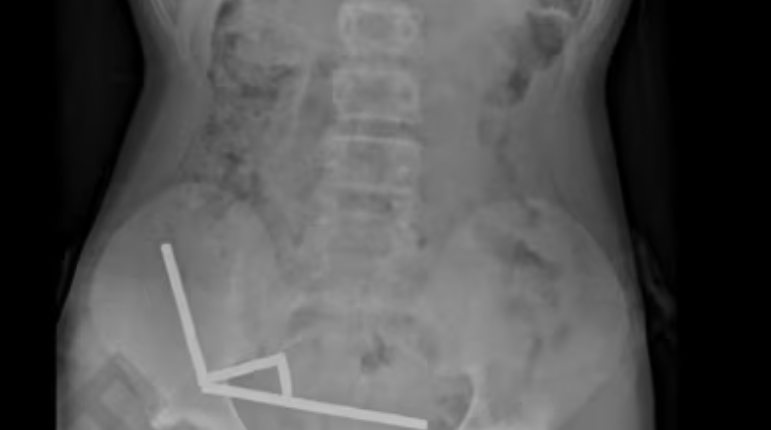

Trinaestogodišnjem dječaku na Novom Zelandu hirurški je odstranjen dio crijeva nakon što je progutao gotovo 200 izuzetno snažnih magneta. Prema riječima ljekara, dječak je otišao u bolnicu Tauranga žaleći se na jake bolove u trbuhu. Priznao je da je progutao stotinjak magneta otprilike sedmicu dana ranije, ali su ljekari kasnije otkrili da ih je zapravo bilo mnogo više, izvještava Science Alert.Magneti su se u njegovom tijelu čvrsto vezali jedan za drugi. Doktori su koristili rendgenske zrake kako bi otkrili četiri lanca magneta, raspoređena po različitim dijelovima njegovih crijeva. Tokom operacije, otkrili su da se ovi lanci nalaze u njegovom tankom crijevu i slijepom crijevu. Budući da su se magneti tako čvrsto vezali, uzrokovali su nedostatak protoka krvi i odumiranje dijela crijevnog tkiva zbog pritiska.

Hirurzi su morali ukloniti dio njegovog crijeva, ali se dječak dobro oporavio i mogao je napustiti bolnicu osam dana nakon operacije.